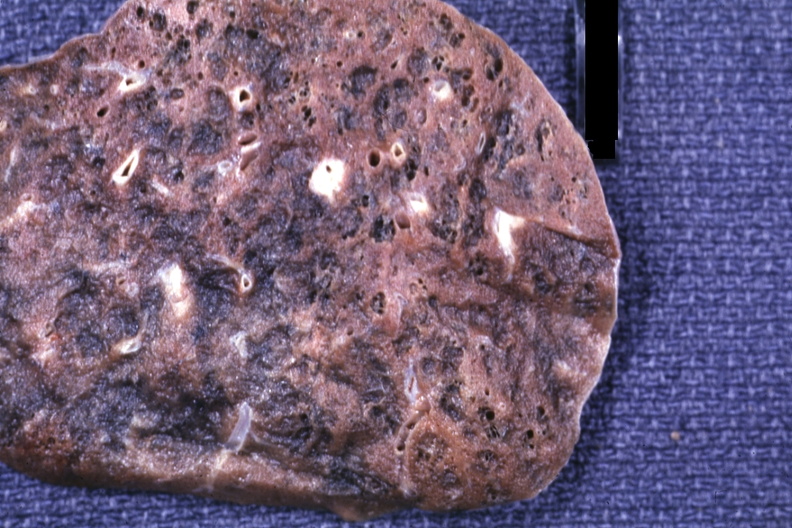

_左下肺肺纖維化病灶

_右肺纖維化病灶

_雙肺肺纖維化肺灶